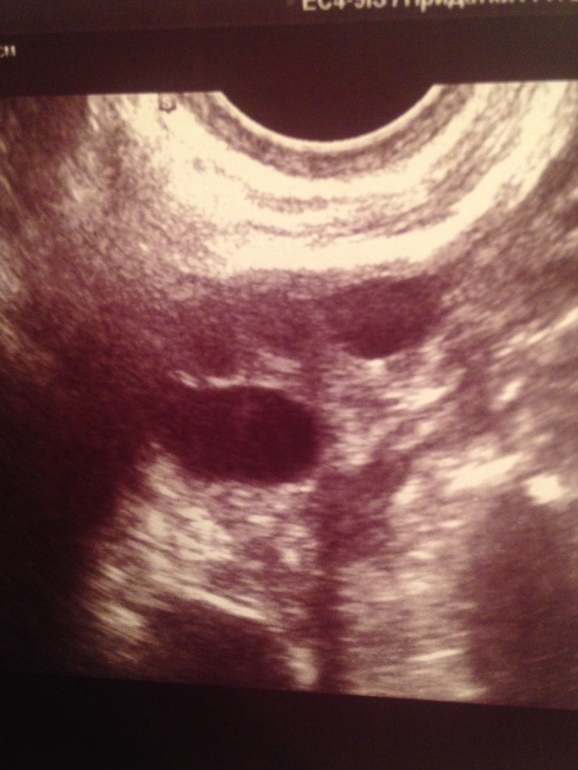

ФолликулометрияДевочки,вчера писала уже,сегодня покажу фото,может кто подскажет,что видите тут?я с телефона и не вижу ,как фото выставились,в комментариях подпишу что есть что.у меня на 16-17 дц эндик второй фазы,анехогенное образование в нем,в ля то ли ДФ ,то от ЖТ.Я вообще в

В заключение вот и написано,что анехогенное образование 1.8 мм(плодное яйцо??) и контроль УЗИ через 2 недели или после М(

Была снова на УЗИ ,обхихаться можно...В Ля вот-вот лопнет фоллик ,в ПЯ ЖТ???,эндик первой фазы и подрос,в нем 2 мм киста под вопросом ...что происходит хах))